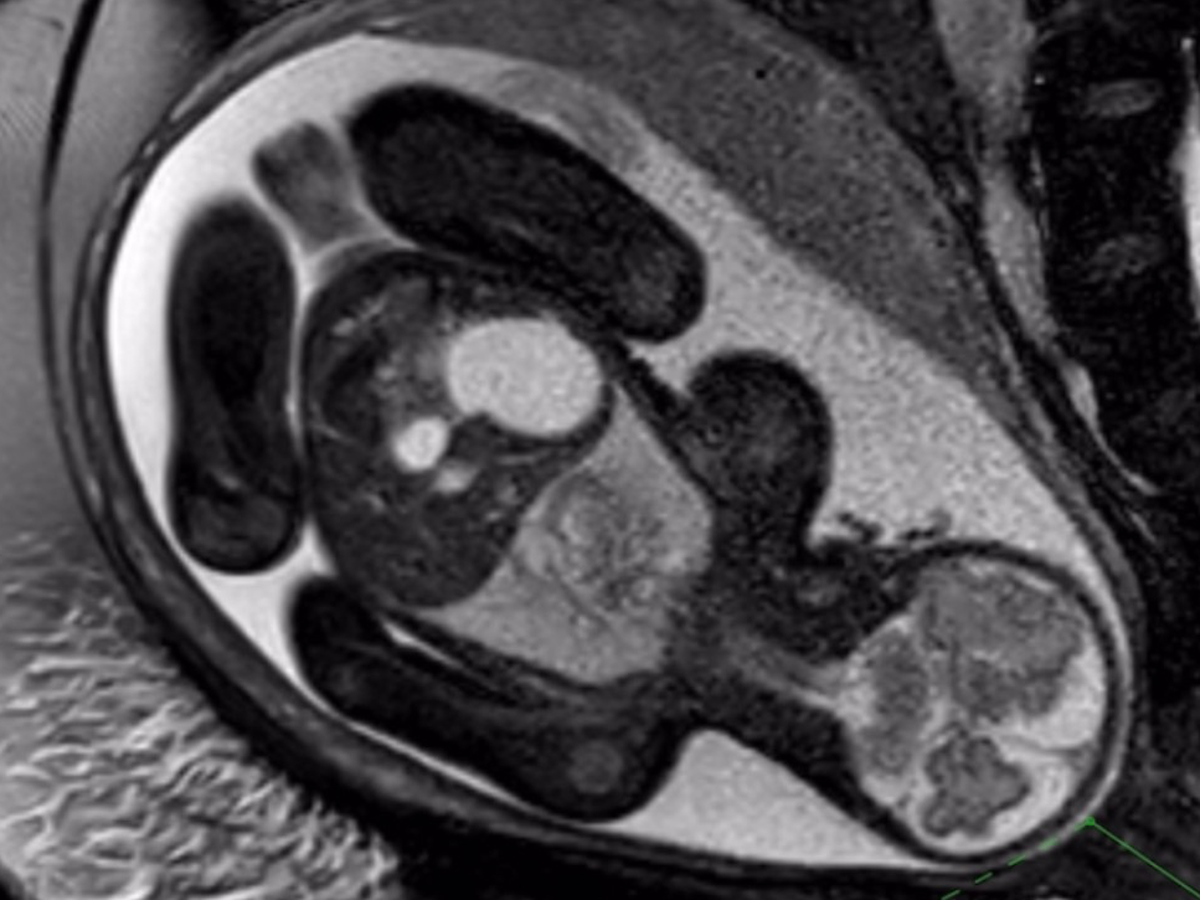

Hi, I’m Jack, and my amazing wife Alicia is now 31 weeks pregnant with our daughter, Sophia Grace. What started as a joyful ultrasound visit, so Alicia’s mom (visiting from California) could see her grandbaby, turned into an unexpected diagnosis at 27 weeks: duodenal atresia, a blockage in Sophia’s small intestine (the “double bubble” sign on MRI).

The great news? Our detailed fetal MRI at Cincinnati Children’s confirmed everything else is perfect; heart, lungs, brain, eyes, spleen, limbs, and strong growth. Genetic testing came back low risk for Down syndrome and other conditions. Sophia is a fighter, and we’re so grateful.